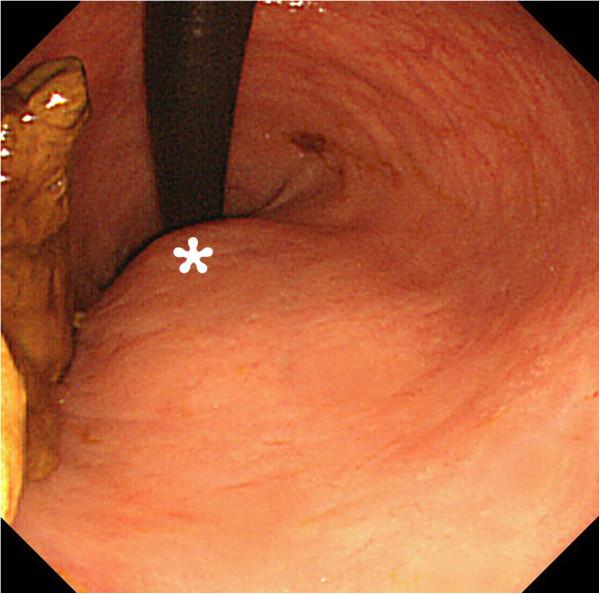

A 32-year-old Japanese man presented with fever, arthralgia and buttock pain. A digital rectal examination showed mild rectal stenosis with local warmth and tenderness in the posterior wall of his rectum. Computed tomography showed a scimitar-shaped deformity of his sacrum and an 8cm presacral mass, which continued to a pedicle of his deformed sacrum. This was diagnosed as Currarino syndrome with a presacral abscess. The abscess was drained by a perianal approach with our patient treated with antibiotics. His symptoms soon disappeared. After three months, an excision was performed through a posterior sagittal approach. His postoperative course was uneventful and he was discharged 10 days after surgery. A histopathological examination revealed an infected epidermoid cyst. He has been free from recurrence as of four years and six months after surgery.

一名32岁的日本男性出现发热、关节痛和臀部疼痛。直肠指检显示直肠轻度狭窄,直肠后壁局部发热和压痛。计算机断层扫描显示其骶骨呈弯刀形畸形,并有一个8厘米的骶前肿块,该肿块延续至其畸形骶骨的一个椎弓根。这被诊断为伴有骶前脓肿的库拉里诺综合征。通过肛周途径引流脓肿,并给予患者抗生素治疗。他的症状很快消失。三个月后,通过后矢状入路进行了切除手术。他的术后病程顺利,术后10天出院。组织病理学检查显示为感染性表皮样囊肿。截至手术四年零六个月,他未出现复发。